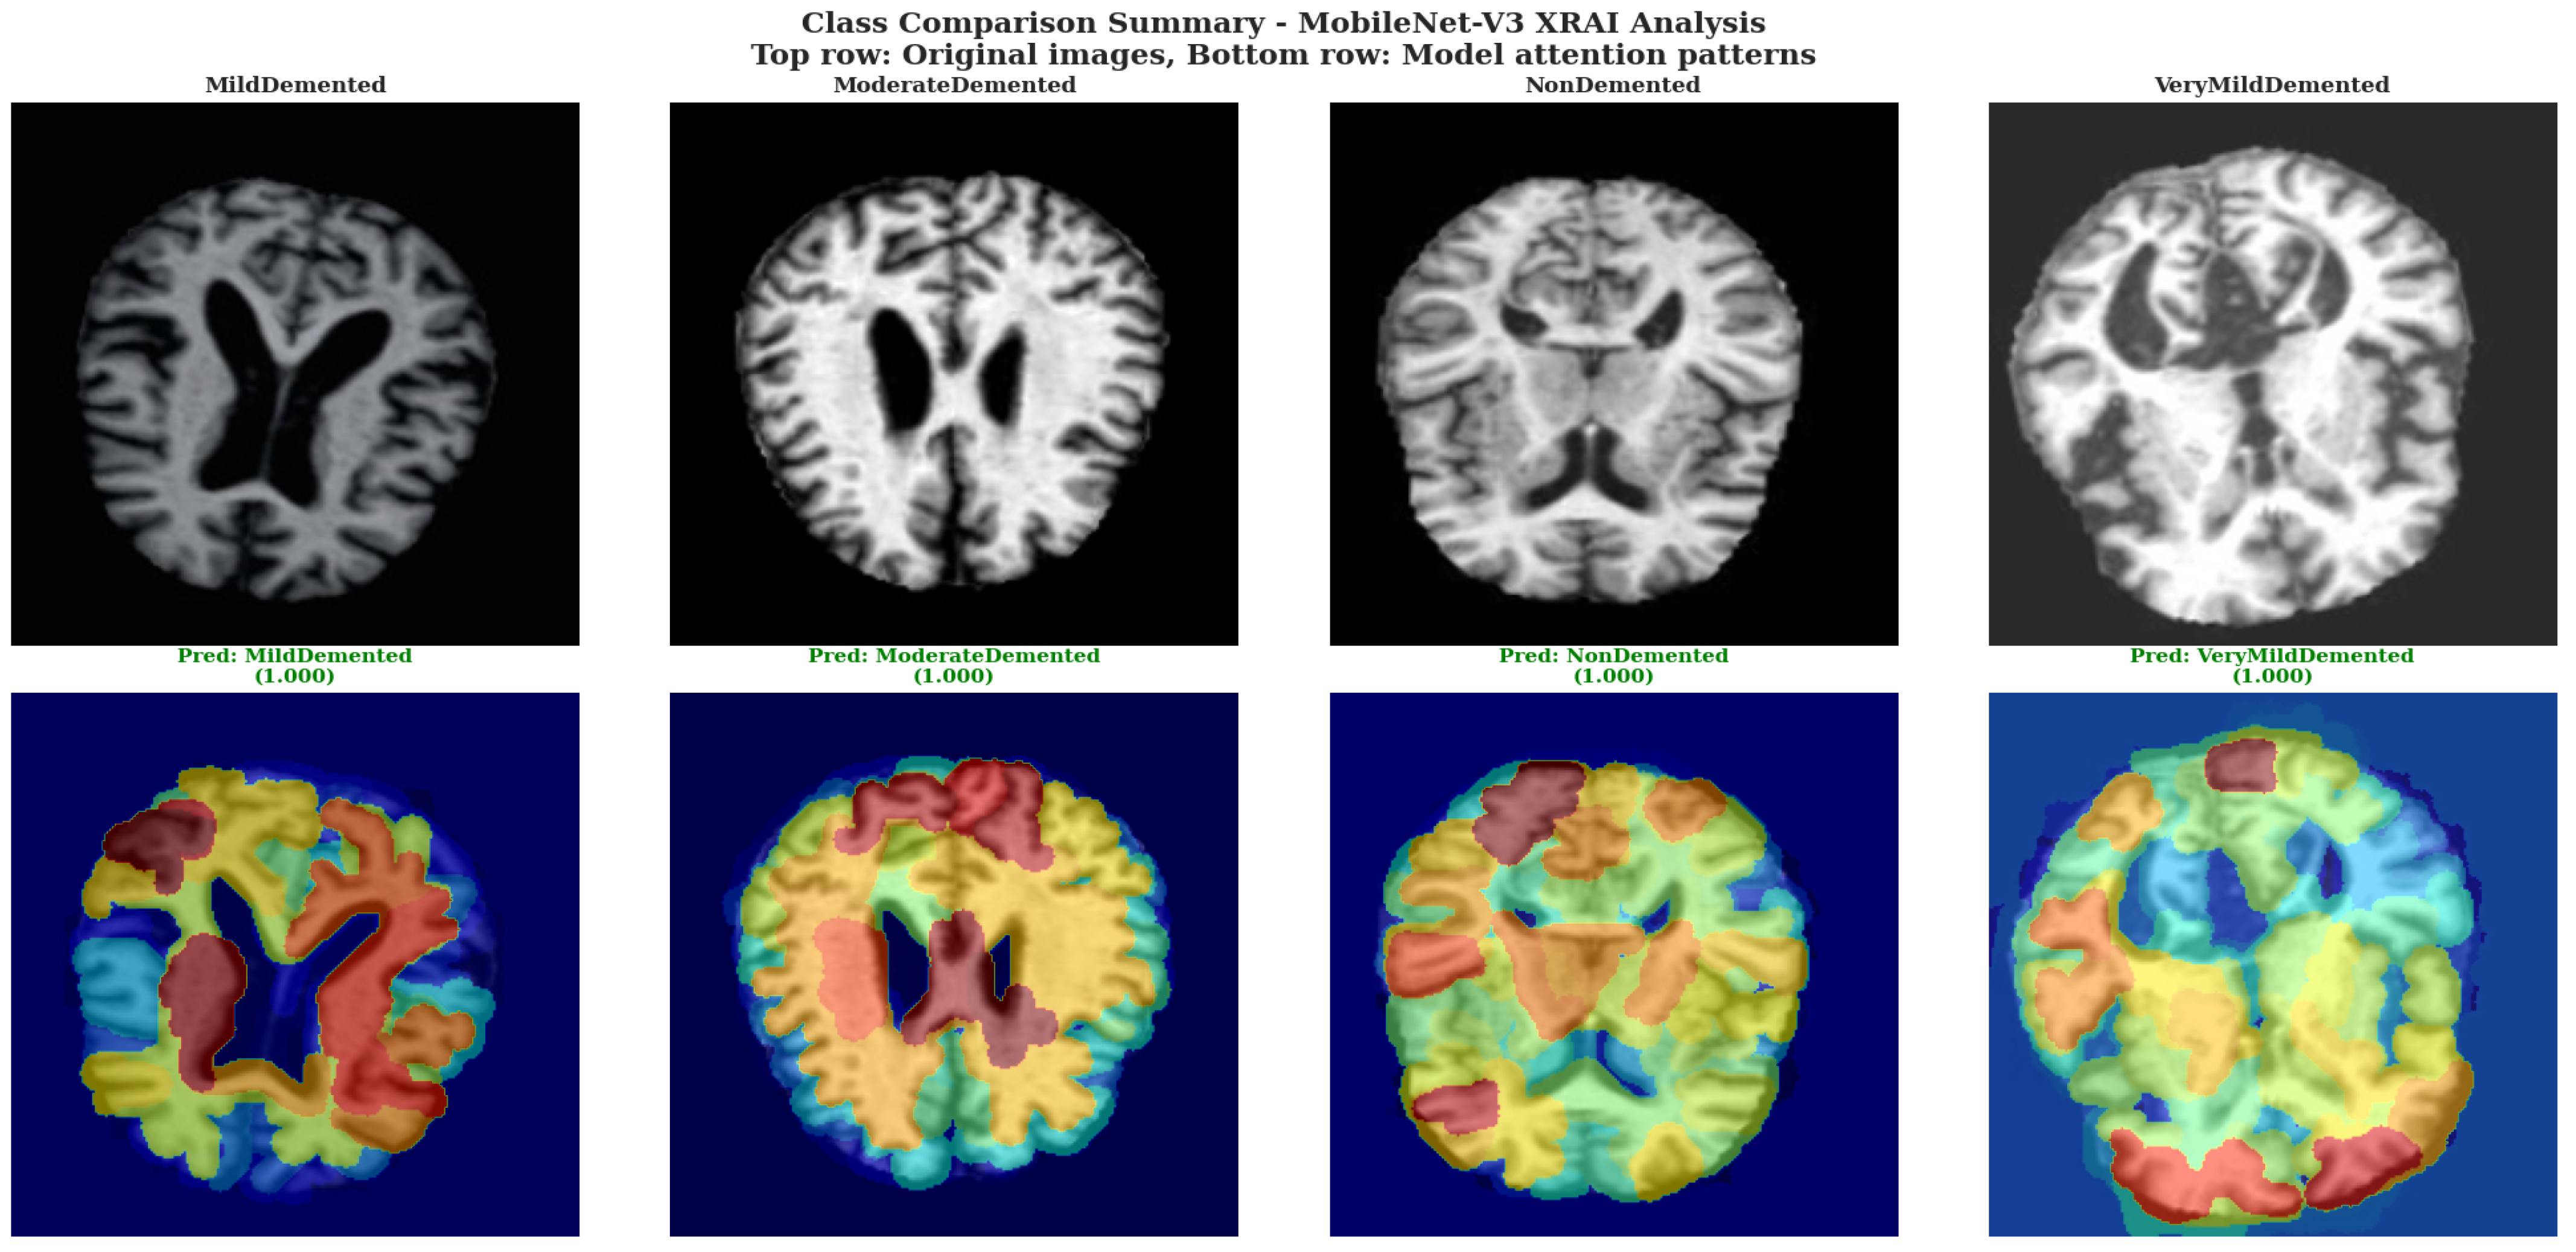

Class Comparison Summary used MobileNet-V3 XRAI Analysis. The top row shows original brain images for each severity class, while the bottom row displays corresponding model attention patterns with prediction confidence scores, demonstrating systematic attention adaptation across the complete spectrum of Alzheimer’s disease severity.

The systematic comparison across severity classes using MobileNet-V3 in Figure 11 revealed distinct attribution pattern characteristics for each dementia stage, demonstrating adaptive model responses to varying input conditions. For the MildDemented case, MobileNet-V3 generated diverse attribution regions with prominent yellow areas in cortical zones and red regions indicating moderate attention levels, creating a heterogeneous pattern that suggests multifocal feature detection. The ModerateDemented case displayed more extensive yellow and orange attribution coverage with concentrated high-attention regions in upper cortical areas, indicating heightened model sensitivity to structural changes characteristic of moderate disease progression.

The NonDemented case exhibited widespread yellow and orange attribution patterns with substantial coverage across cortical regions, demonstrating that MobileNet-V3 actively identifies specific normal tissue characteristics rather than showing minimal attribution for healthy cases. This extensive attribution in healthy brain tissue indicates the model’s sophisticated approach to distinguishing normal anatomical features from pathological changes. The VeryMildDemented case showed balanced attribution distribution with prominent yellow regions in peripheral cortical areas and blue regions in central ventricular spaces, suggesting the model’s capability to detect subtle early pathological markers while maintaining spatial organization that respects anatomical boundaries.

Across all severity levels, MobileNet-V3 demonstrated consistent color mapping behavior with blue regions corresponding to low attribution values in central ventricular areas, yellow and orange regions indicating moderate to high attribution in cortical tissue zones, and red regions marking intermediate attention levels. The attribution overlays maintained consistent registration between original tissue structure and attribution distribution, indicating proper spatial correspondence between model attention and input anatomy while preserving anatomical boundary relationships across all severity classifications.